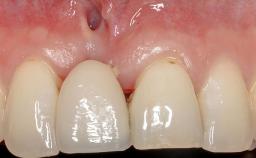

GBR and Soft-Tissue Augmentation Following Explantation to Rehabilitate a Soft- and Hard-Tissue Defect

It is sometimes necessary to remove and replace compromised implants. This case is a clear example of the need for multiple steps to achieve an optimal therapeutic result for patients with non-salvageable implants. It illustrates how the lost soft and hard tissues were rebuilt in a sequence that improved the healing of the hard tissues and assured their long-term stability. The 35-year-old healthy patient presented with clinical attachment loss on the proximal and lingual surfaces of the natural dentition. Some gingival recession was present on natural teeth, particularly in the posterior sextants (S1, S3, S4, and S6).